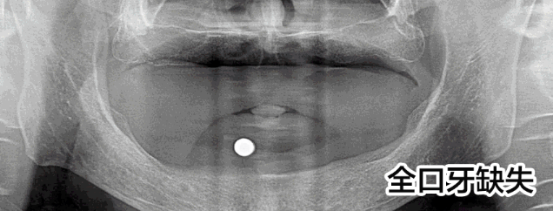

先天性牙缺失修復(fù)案例

趙先生先天性發(fā)育異常導(dǎo)致全口牙缺失,才36歲就掉了好幾顆牙,為此趙先生痛苦:“聽說這是一種病,發(fā)病概率小,但不知道怎么就被我攤上了。我還這么年輕就缺了這么多顆牙,真的很奔潰!”

趙先生的遭遇讓人同情,他尋找了多家醫(yī)院都被告知他由于牙齒缺失沒有進(jìn)行及時(shí)修復(fù)導(dǎo)致他的牙槽骨萎縮,再加上本身骨量不足,無法進(jìn)行牙齒種植。牙齒的問題讓趙先生一度有了輕生的念頭。而這次他通過新聞知道亞洲種植牙大師劉斌元教授來到福州,就抱著希望來到科爾。

劉斌元教授在為趙先生進(jìn)行一系列的檢查后說:“這位患者要做種植牙手術(shù)的話的確復(fù)雜,但是也并非說不能種植,就是操作起來難度大?!?

趙先生的手術(shù)順利,種植牙齒后他覺得整個(gè)人都活過來了。

“當(dāng)時(shí)只是覺得人很舒服,一下子就放松了,之后腦子就是一片空白,手術(shù)進(jìn)行的很快,從進(jìn)入種植間到至后一顆種植牙的植入,只用了短短3個(gè)小時(shí)”,三分鐘改變了趙先生的一生,趙先生感激劉斌元教授:“如果沒有劉斌元教授為我進(jìn)行手術(shù),我都不知道接下來該怎么辦?,F(xiàn)在說什么都不能表達(dá)我的感激之情,但還是要對(duì)劉院長(zhǎng)說一聲謝謝!”

首先,像趙先生這樣的先天性發(fā)育不良造成的全口牙缺失的病例本身就是很罕見的,可以說是幾十年難遇。其次,全口牙缺失本身就屬于牙科領(lǐng)域中難的一種技術(shù)。沒有先進(jìn)的高精口腔CT技術(shù)的保障,在傳統(tǒng)的診療條件下,很難手術(shù)的。因而,在硬件、設(shè)備、技術(shù)還不成熟的情況下,并不是所有醫(yī)院都能完成這種病例的調(diào)節(jié)。因此,在做全口牙種植前,選擇正規(guī)的醫(yī)院和臨床經(jīng)驗(yàn)豐富的醫(yī)生,是保障手術(shù)成功的先決條件。